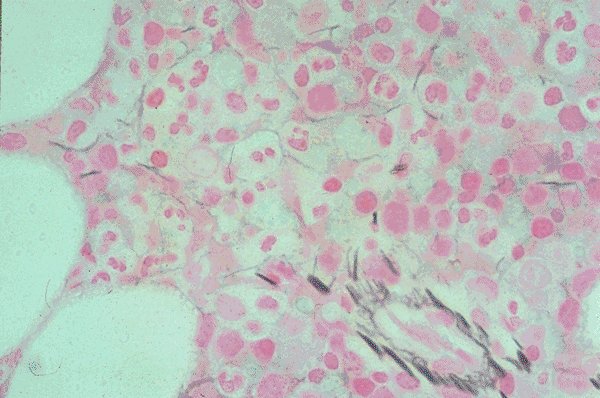

Slide 3 of 192 Image ID 520

Keywords

Normal marrow

Description

This is a power view of a normal bone marrow

biopsy stained for reticulin. The fibers are seen in

a somewhat normal distribution and show up with

a darker stain.